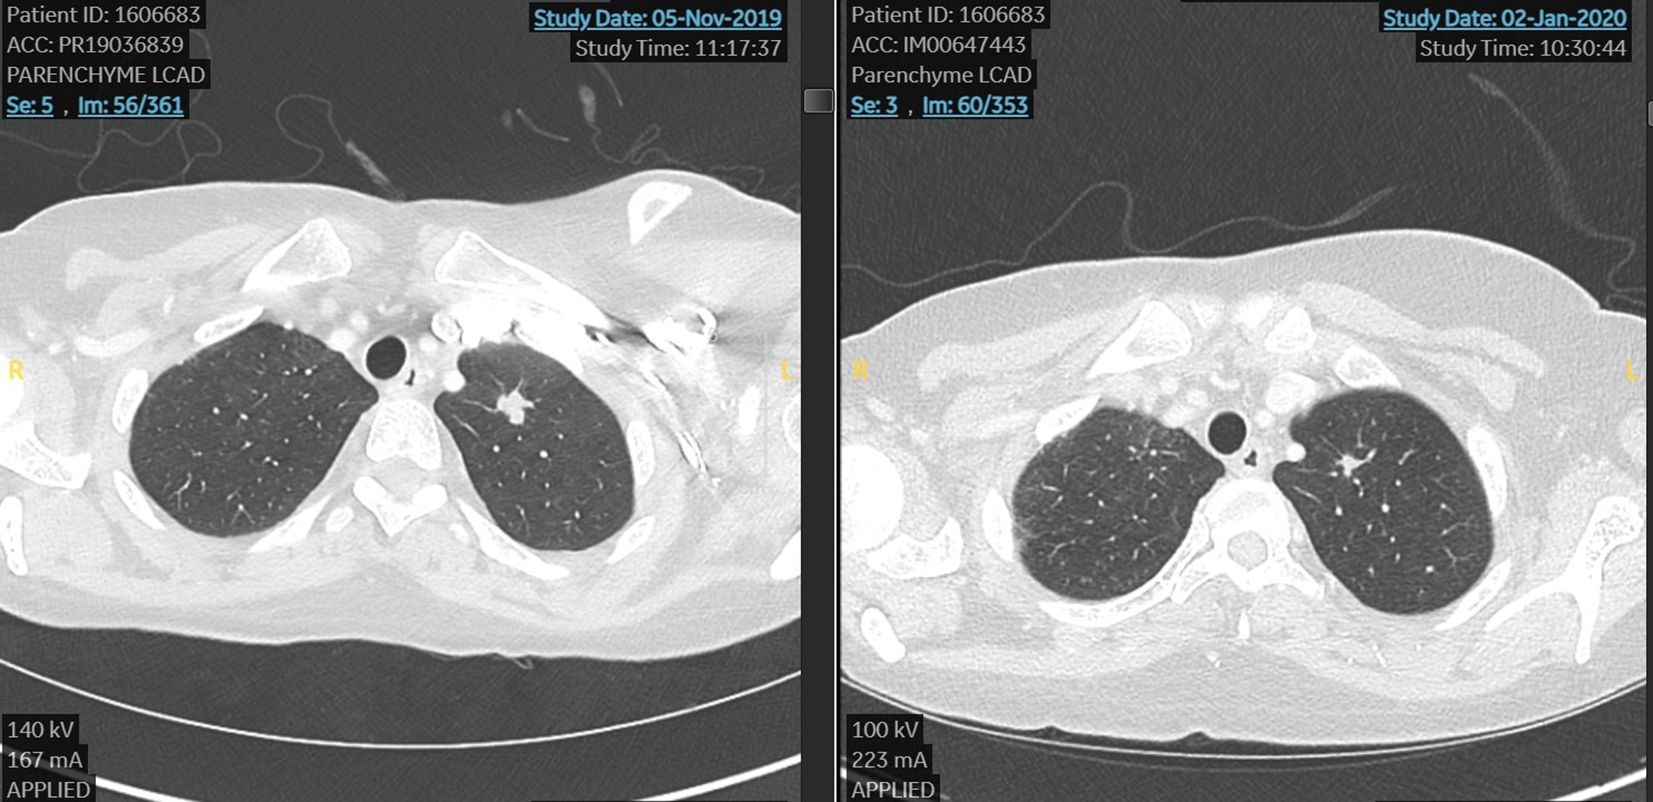

In November 2019 due to the bone, node, and lung progression disease, she was considered for a DAISY study and she was randomized to the experimental arm and treated with DS82 (trastuzumab deruxtecan). She reached a very early benefit in skin lesions (after 3 weeks) and a partial response by RECIST 1.1 at the first scan after 6 weeks of treatment (Figure 1).

Figure 1. First case. Lung metastasis at the start and after 6 weeks of treatment with TDX-d (partial response by RECIST 1.1).